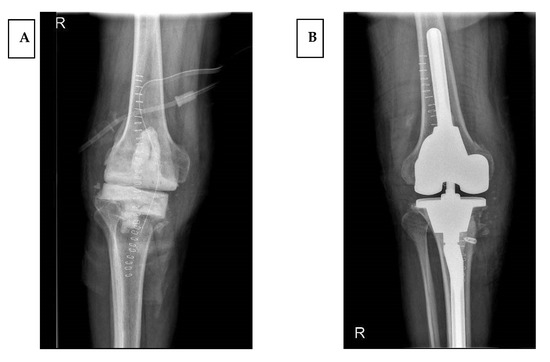

Prosthetic infection was diagnosed following the Musculoskeletal Infection Society (MSIS) criteria [12], and each infection case underwent a two-stage procedure (Figure 1).

Figure 1. Two-step revision surgery in periprosthetic infection. Stage one (A), and definitive implant positioning (B).